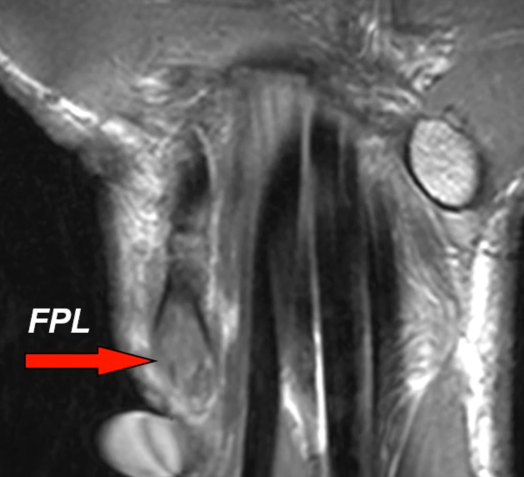

Tenosynovite de la jeune maman (de Quervain)

- Ténosynovite du premier compartiment

- Mères qui portent leur enfant ++

- Inflammation des tendons au niveau de la styloide radiale

tendon extenseur teno téno bebe enfant bébé berce berçant